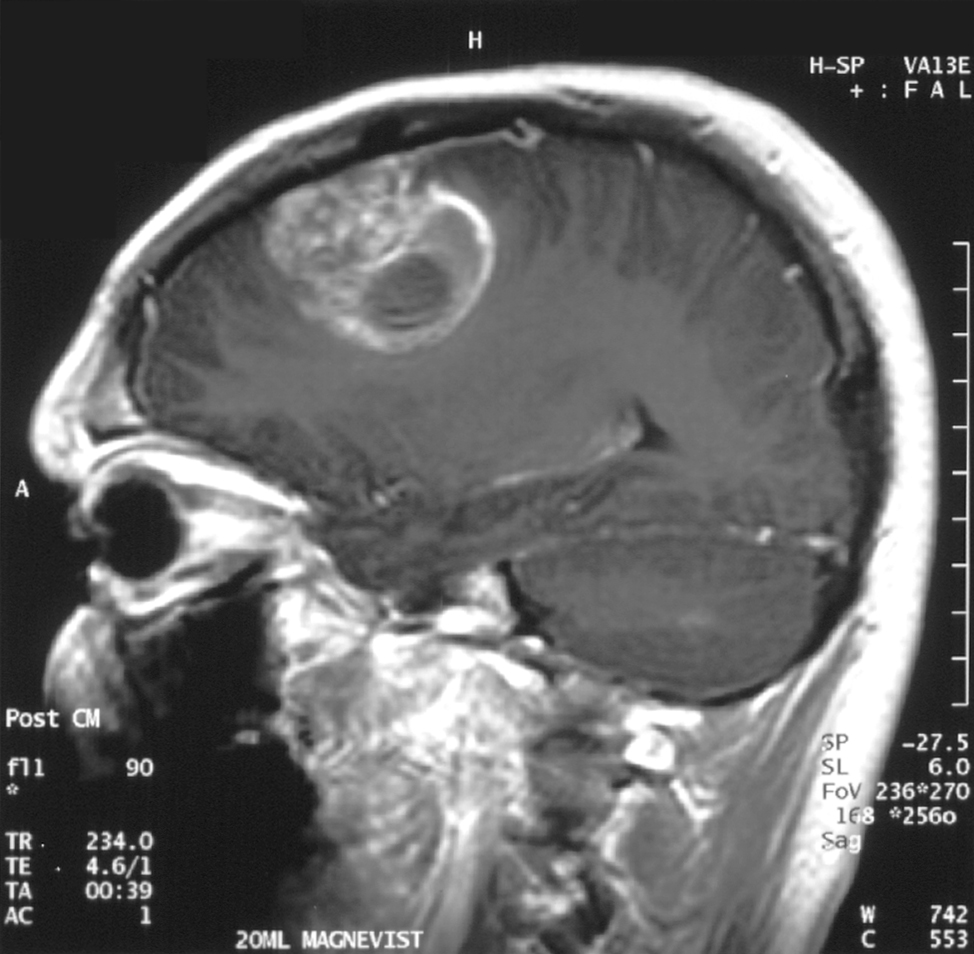

신경교 세포(주로 별아교 세포)에서 기원하는 악성 종양 중, 극도로 미분화되어 증식 능력이 높은 것을 교모세포종이라 한다. 종양은 출혈을 동반하는 경우가 많으며, 종양 내부에 괴사 덩어리가 관찰되기도 한다. 종양 세포는 원형, 방추형 등 다양한 형태를 가지며, 크기가 일정하지 않다.

MRI로 볼 때, 교모세포종은 종종 환상 강화 병변으로 나타난다. 그러나 농양, 전이, 종괴성 다발성 경화증 등도 유사한 모습을 보일 수 있어 이 모습만으로는 특정할 수 없다.[61] CT 또는 MRI에서 교모세포종으로 의심되는 질환의 확진은 정위 생검 또는 종양 절제 및 병리적 확인을 위한 개두술이 필요하다. 종양 등급은 종양의 가장 악성인 부분에 기반하므로, 생검 또는 아전 절제술은 병변의 등급을 낮게 평가하는 결과를 초래할 수 있다.

5. 2. 조직 검사